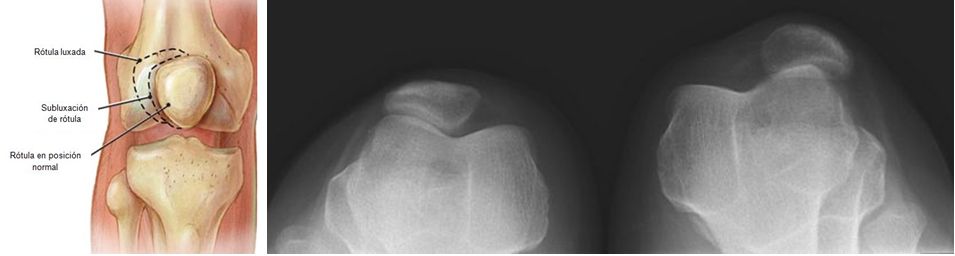

Subluxación rotuliana es el diagnóstico más probable en una adolescente que presenta  episodios de la rodilla inestable.

Esta lesión es más frecuente en las niñas y mujeres jóvenes a causa de un aumento del ángulo del cuádriceps (ángulo Q - figura), por lo general mayor de 15 grados.

La compresión rotuliana se produce con la subluxación de la rótula lateralmente, y suele estar presente un leve derrame. Inflamación de la rodilla moderada a severa puede indicar hemartrosis, lo que sugiere la luxación patelar con fractura osteocondral y sangrado.